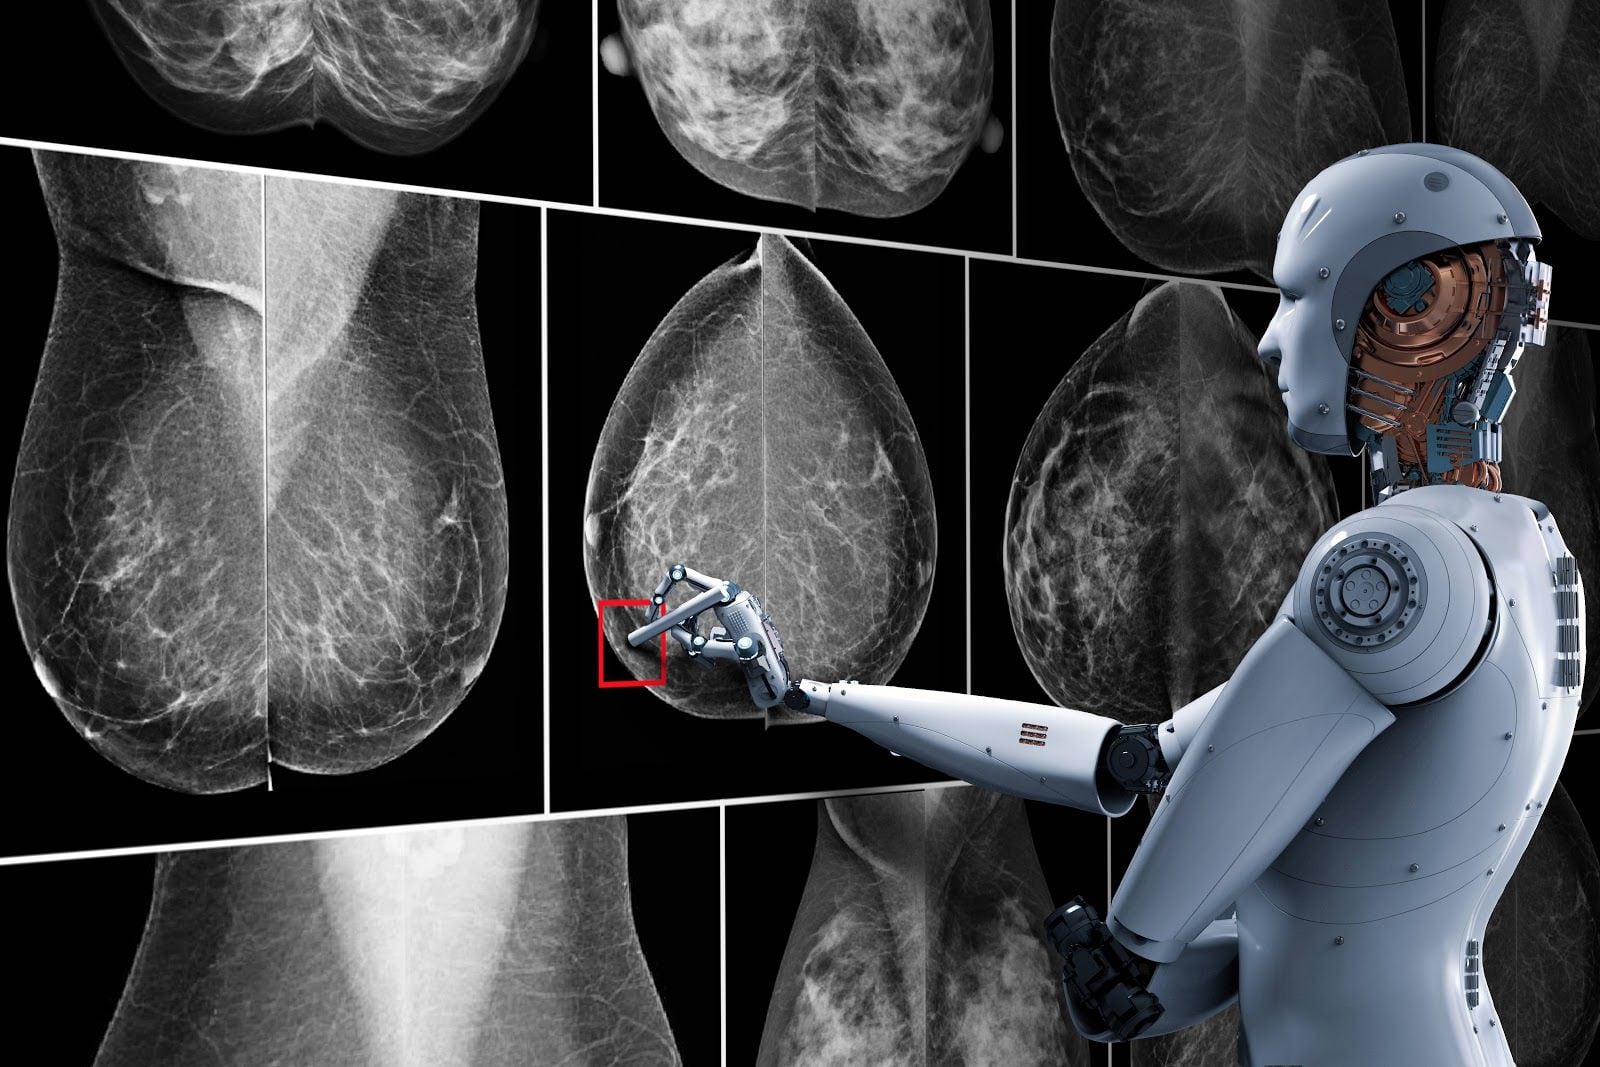

Casi a diario, nuevas investigaciones científicas demuestran la importancia de la inteligencia artificial en la medicina, ya que permite no solo analizar datos a gran escala, sino también detectar con mayor precisión y velocidad distintas patologías. En este sentido, una investigación realizada por científicos suecos advirtió que la IA puede ser aún más eficaz que los métodos tradicionales de lectura de mamografías.

Un estudio publicado en The Lancet, realizado en cuatro sitios de detección en Suecia a más de 80.033 mujeres de entre 40 y 80 años, advirtió que la IA identificó un 20% más de cánceres en comparación con la revisión estándar efectuada por expertos humanos.

La IA en mamografías puede revolucionar la lucha contra el cáncer de mama (foto: El Chapuzas Informático)

La IA en mamografías puede revolucionar la lucha contra el cáncer de mama (foto: El Chapuzas Informático)Según explicaron, se trató de un ensayo aleatorizado y controlado, en el cual las participantes fueron asignadas aleatoriamente a grupos que recibieron detección asistida por IA o lectura doble estándar sin IA.

Los resultados mostraron que la detección por IA identificó 244 cánceres en comparación con 203 detectados en el grupo de control, siendo que las tasas de falsos positivos fueron similares en ambos grupos.

“El Valor Predictivo Positivo (VPP) del recuerdo fue del 28,3% en el grupo de intervención y del 24,8% en el grupo de control”, indicaron en el documento. Y agregaron: “La carga de trabajo de lectura de pantalla se redujo en un 44,3 % con la IA”.

La inteligencia artificial y el aprendizaje automático hoy se utilizan en la oncología, y ayudan acelerar la búsqueda de nueva información y en ordenarla (Getty Images)En ese sentido, según se desprende del trabajo, la tasa de detección de cáncer en el grupo de intervención con IA fue aproximadamente un 0,61%, mientras que en el grupo de control sin IA fue aproximadamente un 0,51%. Esto representa una diferencia del 0,10% a favor del grupo con IA. Es decir que la detección en el grupo de intervención fue aproximadamente un 20% mayor.

En ese sentido, Kaen agregó: “Hoy hay ciertas especialidades dentro de los tratamientos del cáncer, como por ejemplo los diagnósticos por imágenes, en donde la inteligencia artificial ayuda a encontrar alteraciones en las tomografías, en las mamografías. En esos ámbitos, en donde a veces se generaban dudas, la inteligencia artificial ayuda a unificar todo y a empezar a dividir la patología benignas y las patologías malignas”.